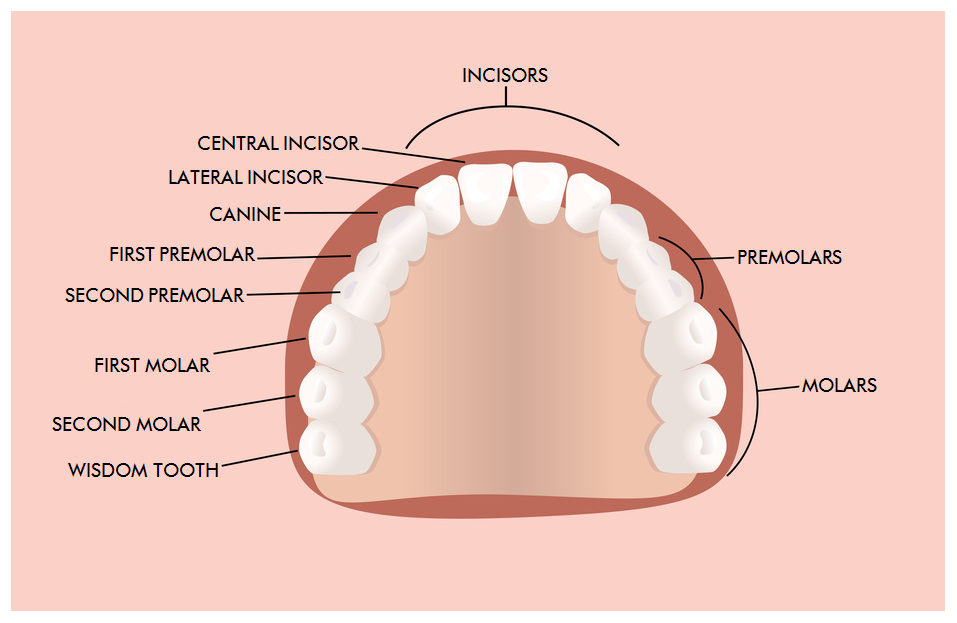

Dentition

A complete dentition consists of 16 teeth in the upper jaw and 16 teeth in the lower jaw.